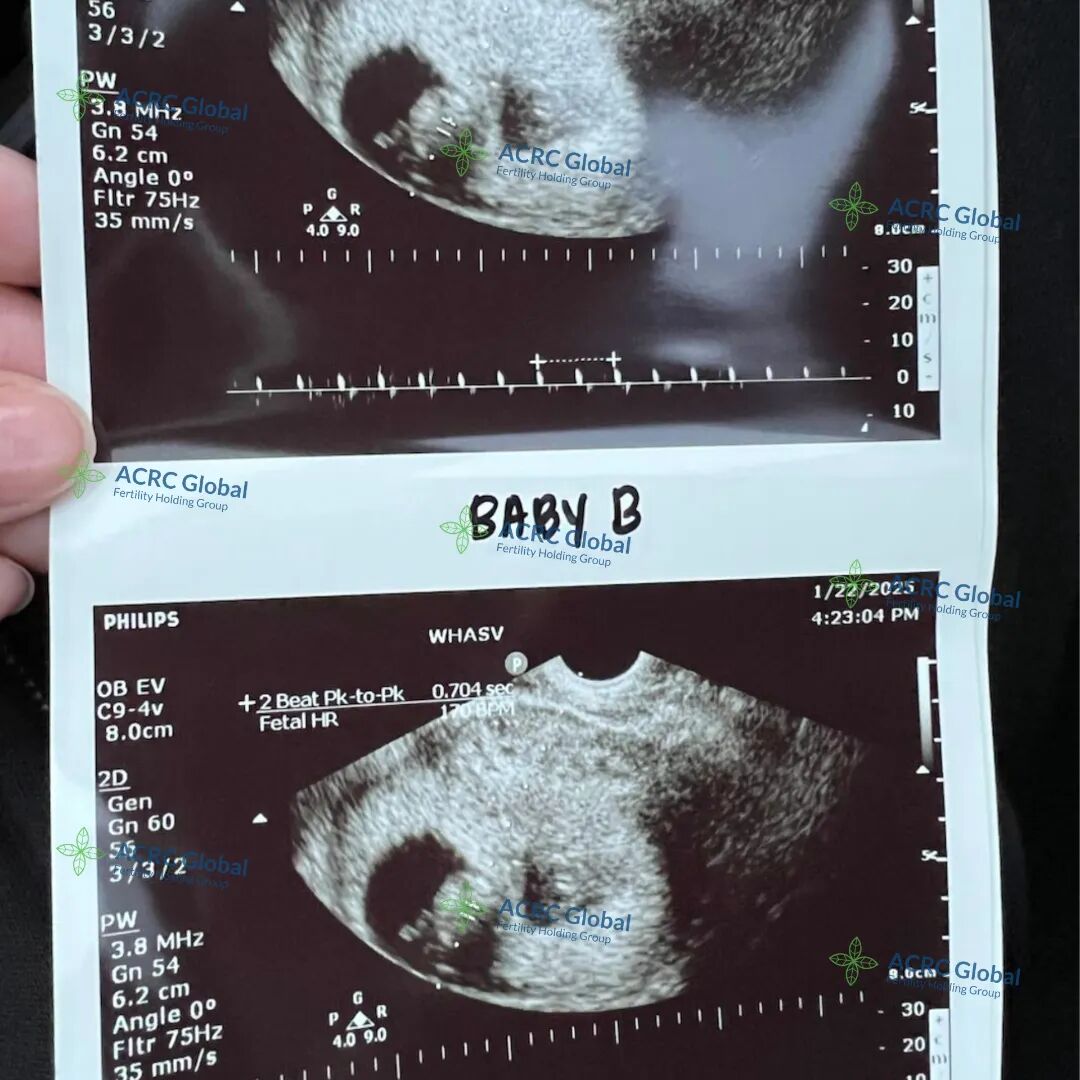

爱妈V的双胎移植也迎来了B超检查,两个宝宝都顺利着床了,宝宝A看起来非常活泼,一直在动,宝宝B则显得格外冷静,两个宝贝性格差异已经初见端倪,实在太有趣了!两位准爸爸听到这个好消息激动不已,已经约定好下一次产检时一同到场,为爱妈加油打气,给予满满支持!